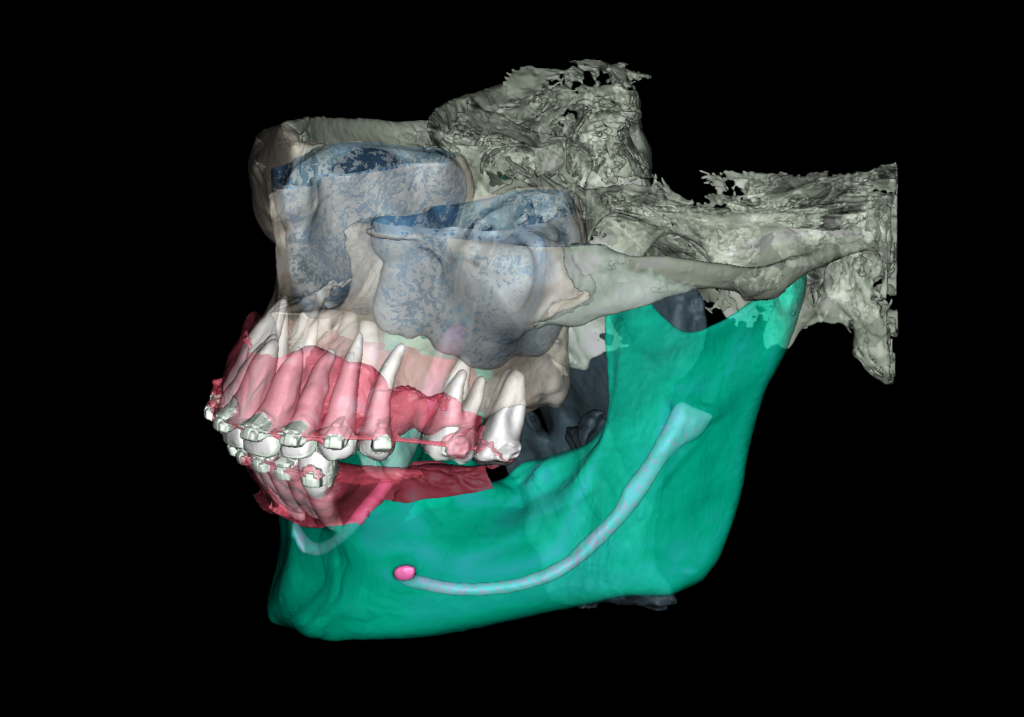

To plan implant treatment for the replacement of tooth 25 (Universal 13), the intraoral scanning data was uploaded into the STL module and obtain a 3D model for selecting the optimal spatial position of the implant and planning the virtual design of the template

Fully automatic segmentation and creation of 3D models from DICOM files allows you to select individual structures for printing models on a 3D printer